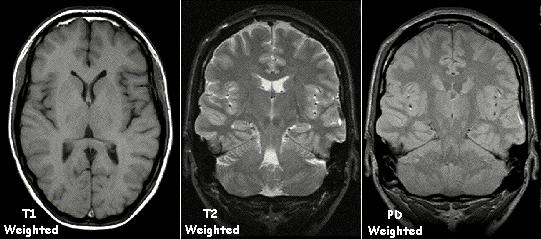

T1和T2弛豫:MRI的"语言"

MRI最神奇的地方在于,它可以通过调整扫描参数,获得不同"对比度"的图像。这主要依赖于两种弛豫过程:

T1弛豫(纵向弛豫)

- 氢原子核恢复到平衡状态的速度

- T1加权图像:脂肪呈高信号(亮),水呈低信号(暗)

- 适合观察解剖结构

T2弛豫(横向弛豫)

- 氢原子核之间相位一致性丧失的速度

- T2加权图像:水呈高信号(亮),脂肪呈中等信号

- 适合观察病变(如水肿、肿瘤)

同一层面的T1加权、T2加权和质子密度(PD)加权MRI图像对比,不同加权方式下组织信号强度差异明显

📊 T1和T2的临床意义

| 组织类型 | T1加权 | T2加权 | 临床应用 |

|---|---|---|---|

| 脂肪 | 高信号(亮) | 中等信号 | 解剖结构 |

| 水/脑脊液 | 低信号(暗) | 高信号(亮) | 水肿、积液 |

| 灰质 | 中等信号 | 中等信号 | 脑组织对比 |

| 白质 | 高信号 | 低信号 | 脱髓鞘病变 |

| 肿瘤 | 低-中等信号 | 高信号 | 肿瘤检测 |